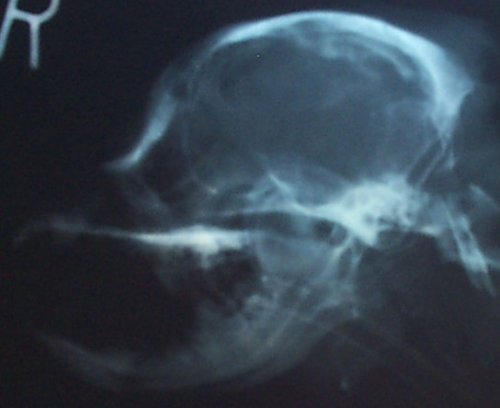

Based on my findings, a study was eventually done to determine

if a skull x-ray could be used to determine amount of CM. The

more CM, the more likely there is to be SM--in most cases. This

study did show there was one skull measurement that did indicate

amount of CM. Here is a comparison of two skull x-rays which

show why this particular measurement indicates amount of CM. The

top one is a skull x-ray of a Cavalier with severe CM (and has

SM as well) and the bottom one is a skull x-ray of a Cavalier

with very little to no CM (and no SM).

The line was drawn from right in front of the 'hole'

(black spot), center of that curved bone (the 'jaw hinge' area)

to where the most thickened area of the skull ends (and the

occipital area begins). In the dog with almost no CM and no SM

you can CLEARLY see there is a lot more lower backskull left

behind/below that line as compared to the dog above--which

literally has almost none! This also happens to be the area

where the cerebellum sits so it would be common sense that the

dog in the top x-ray would have much less room for the

cerebellum than the dog on the bottom--and therefore more CM (chiari

malformation). There just isn't any skull left for there to be

enough room for the cerebellum. It appears here that a good

skull x-ray may be very useful in determining amount of CM and

therefore breeding towards a goal of less and less CM in future

offspring and thereby lessening the prevalence of SM. A skull

x-ray is much cheaper than an MRI which will enable many more

breeders to x-ray for amount of CM in the future as more

information becomes available.